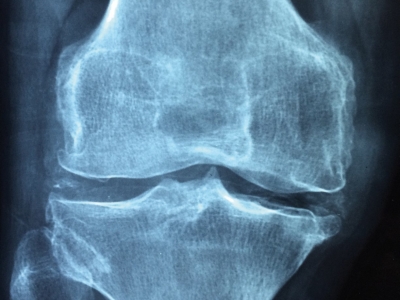

Von der Therapie zum Training: Die Diagnose

Krankheitsbild Arthrose